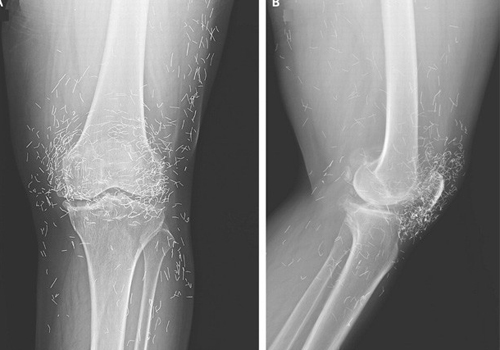

Uma radiografia divulgada pela instituição mostrou o joelho da sul-coreana cercado de diversos fragmentos de agulhas.

Radiografia mostra agulhas | Foto: Divulgação/New England Journal of Medicine)